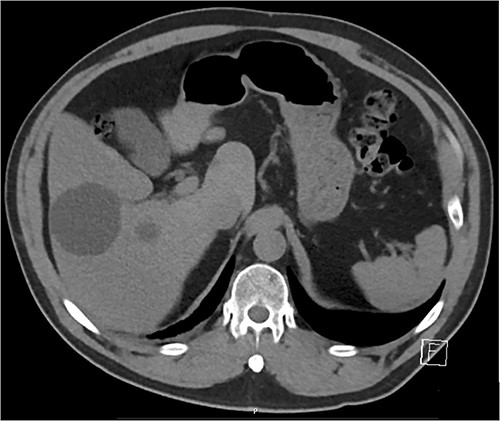

On examination, he appeared well, with no oxygen requirement and reduced air entry in the right mid to lower chest. A chest X-ray (Fig. 1) showed a large cavitating lesion in the right lower zone with a chest computed tomography (CT; Fig. 2) confirming a large lung lesion measuring 100 mm × 80 mm × 100 mm with surrounding ground glass changes. Tests for SARS-CoV-2 and hydatid serology returned positive. He proceeded to have a bronchoscopy and bronchoalveolar lavage that was negative for aspergillus, galactomannan, mycobacterial and fungal cultures, cryptococcus, respiratory viral panel and cytology. A CT abdomen (Fig. 3) revealed multiple hepatic cysts with the largest measuring 59 mm in size in the right lobe. Given the findings of lung and liver lesions, he was commenced on albendazole for presumed extra-hepatic hydatid disease and referred to the cardiothoracic team for resection of the pulmonary hydatid cyst.